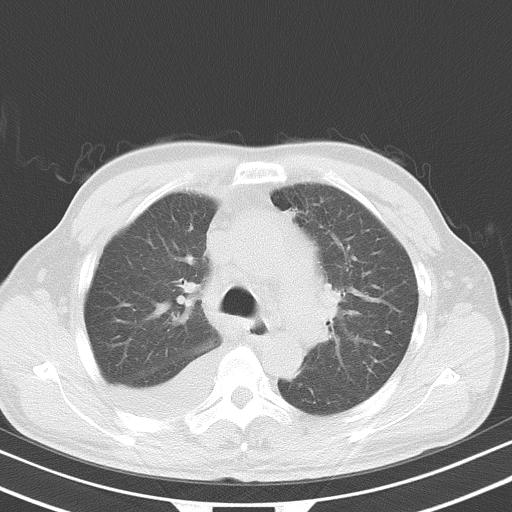

以下是引用zjzjr在2010-3-21 17:39:00的发言:[br]右下中心型肺癌并阻塞性肺炎/不张,纵膈淋巴结肿大,右侧大量胸腔积液,左侧少量胸腔积液

以下是引用zxl51642在2010-3-21 17:06:00的发言:[br]右下中心型肺癌并阻塞性肺炎/不张,纵膈淋巴结肿大,右侧大量胸腔积液,左侧少量胸腔积液,少量腹水。建议纤维支气管镜进一步检查。